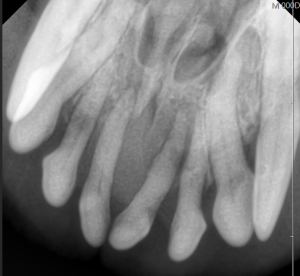

先日、ビルバック社より新たに発売される犬の新しい耳科治療薬の発売記念イベントに参加してきました。

日本は耳科診療の先進国だと感じております。今後も、世界をリードする耳科処置を提供できるよう、精進してまります。